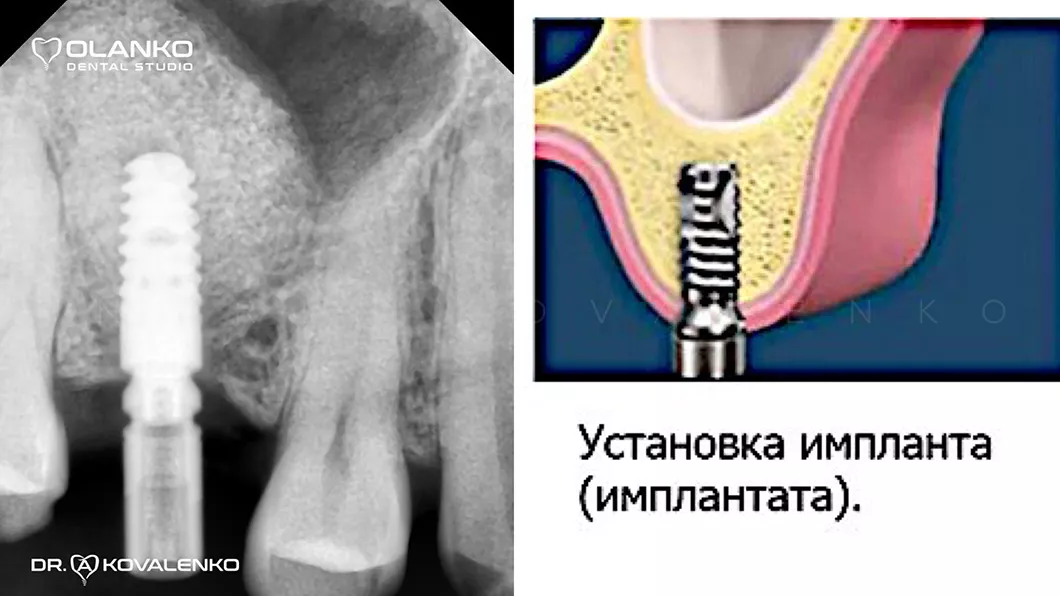

Кісткова пластика щелепи - установка імпланта Оланко Бровари Київ